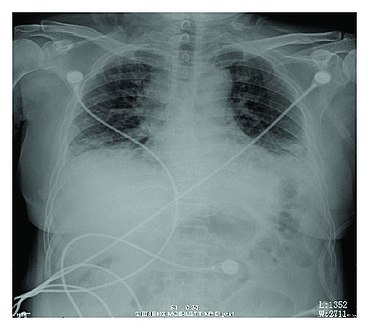

Rapid progression from initial symptoms to respiratory failure is a key feature. An X-ray that shows ARDS is necessary for diagnosis (fluid in the small air sacs (alveoli) in both lungs). In addition, a biopsy of the lung that shows organizing diffuse alveolar damage is required for diagnosis. This type of alveolar damage can be attributed to nonconcentrated and nonlocalized alveoli damage, marked alveolar septal edema with inflammatory cell infiltration, fibroblast proliferation, occasional hyaline membranes, and thickening of the alveolar walls. The septa are lined with atypical, hyperplastic type II pneumocytes, thus leading to the collapse of airspaces. Other diagnostic tests are useful in excluding other similar conditions, but history, X-ray, and biopsy are essential. These other tests may include basic blood work, blood cultures, and bronchoalveolar lavage.[citation needed] The clinical picture is similar to ARDS, but AIP differs from ARDS in that the cause for AIP is not known.